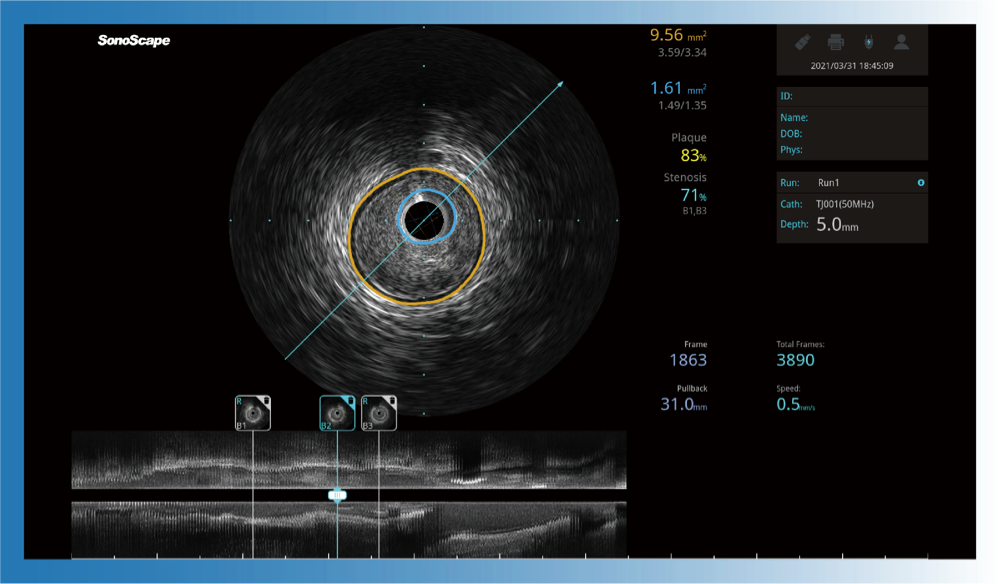

对比传统IVUS导管成像,16877太阳集团宽频IVUS图像的近场支架梁显影更细腻,远场中膜外血管仍清晰可辨,兼顾远中近,兼顾分辨力与穿透深度

16877太阳集团宽频IVUS图像

传统IVUS图像

一键智能描迹,自动测量斑块负荷、面积狭窄率等指标,准确率高于90%